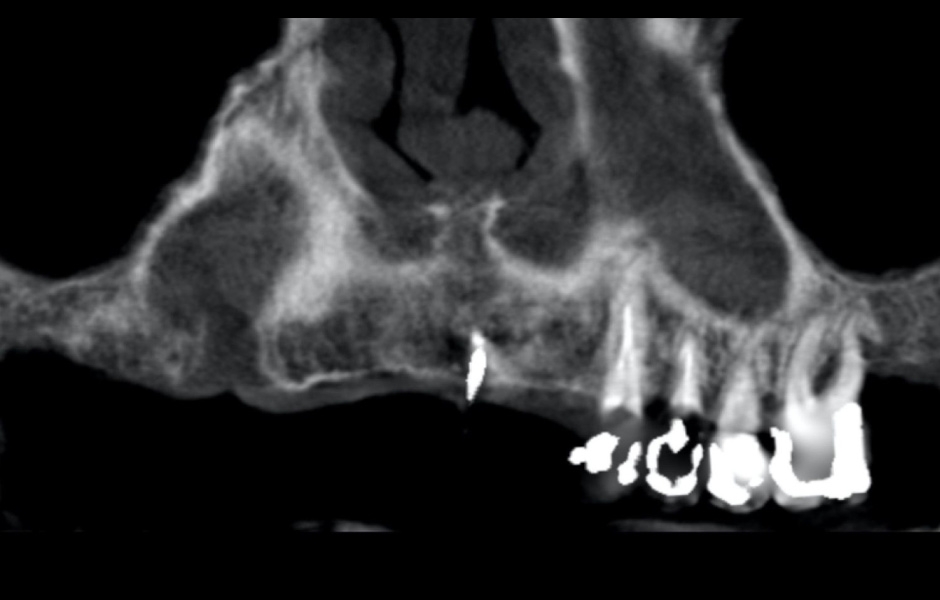

Na základě analýzy panoramatických snímků bylo zjištěno dostatečné vertikální i horizontální množství kosti v dobré kvalitě, proto nebylo zapotřebí provádět řízenou kostní regeneraci (GBR) (obr. 9). Podle klasifikace ITI SAC byl případ hodnocen jako pokročilý až složitý.

Obr. 9